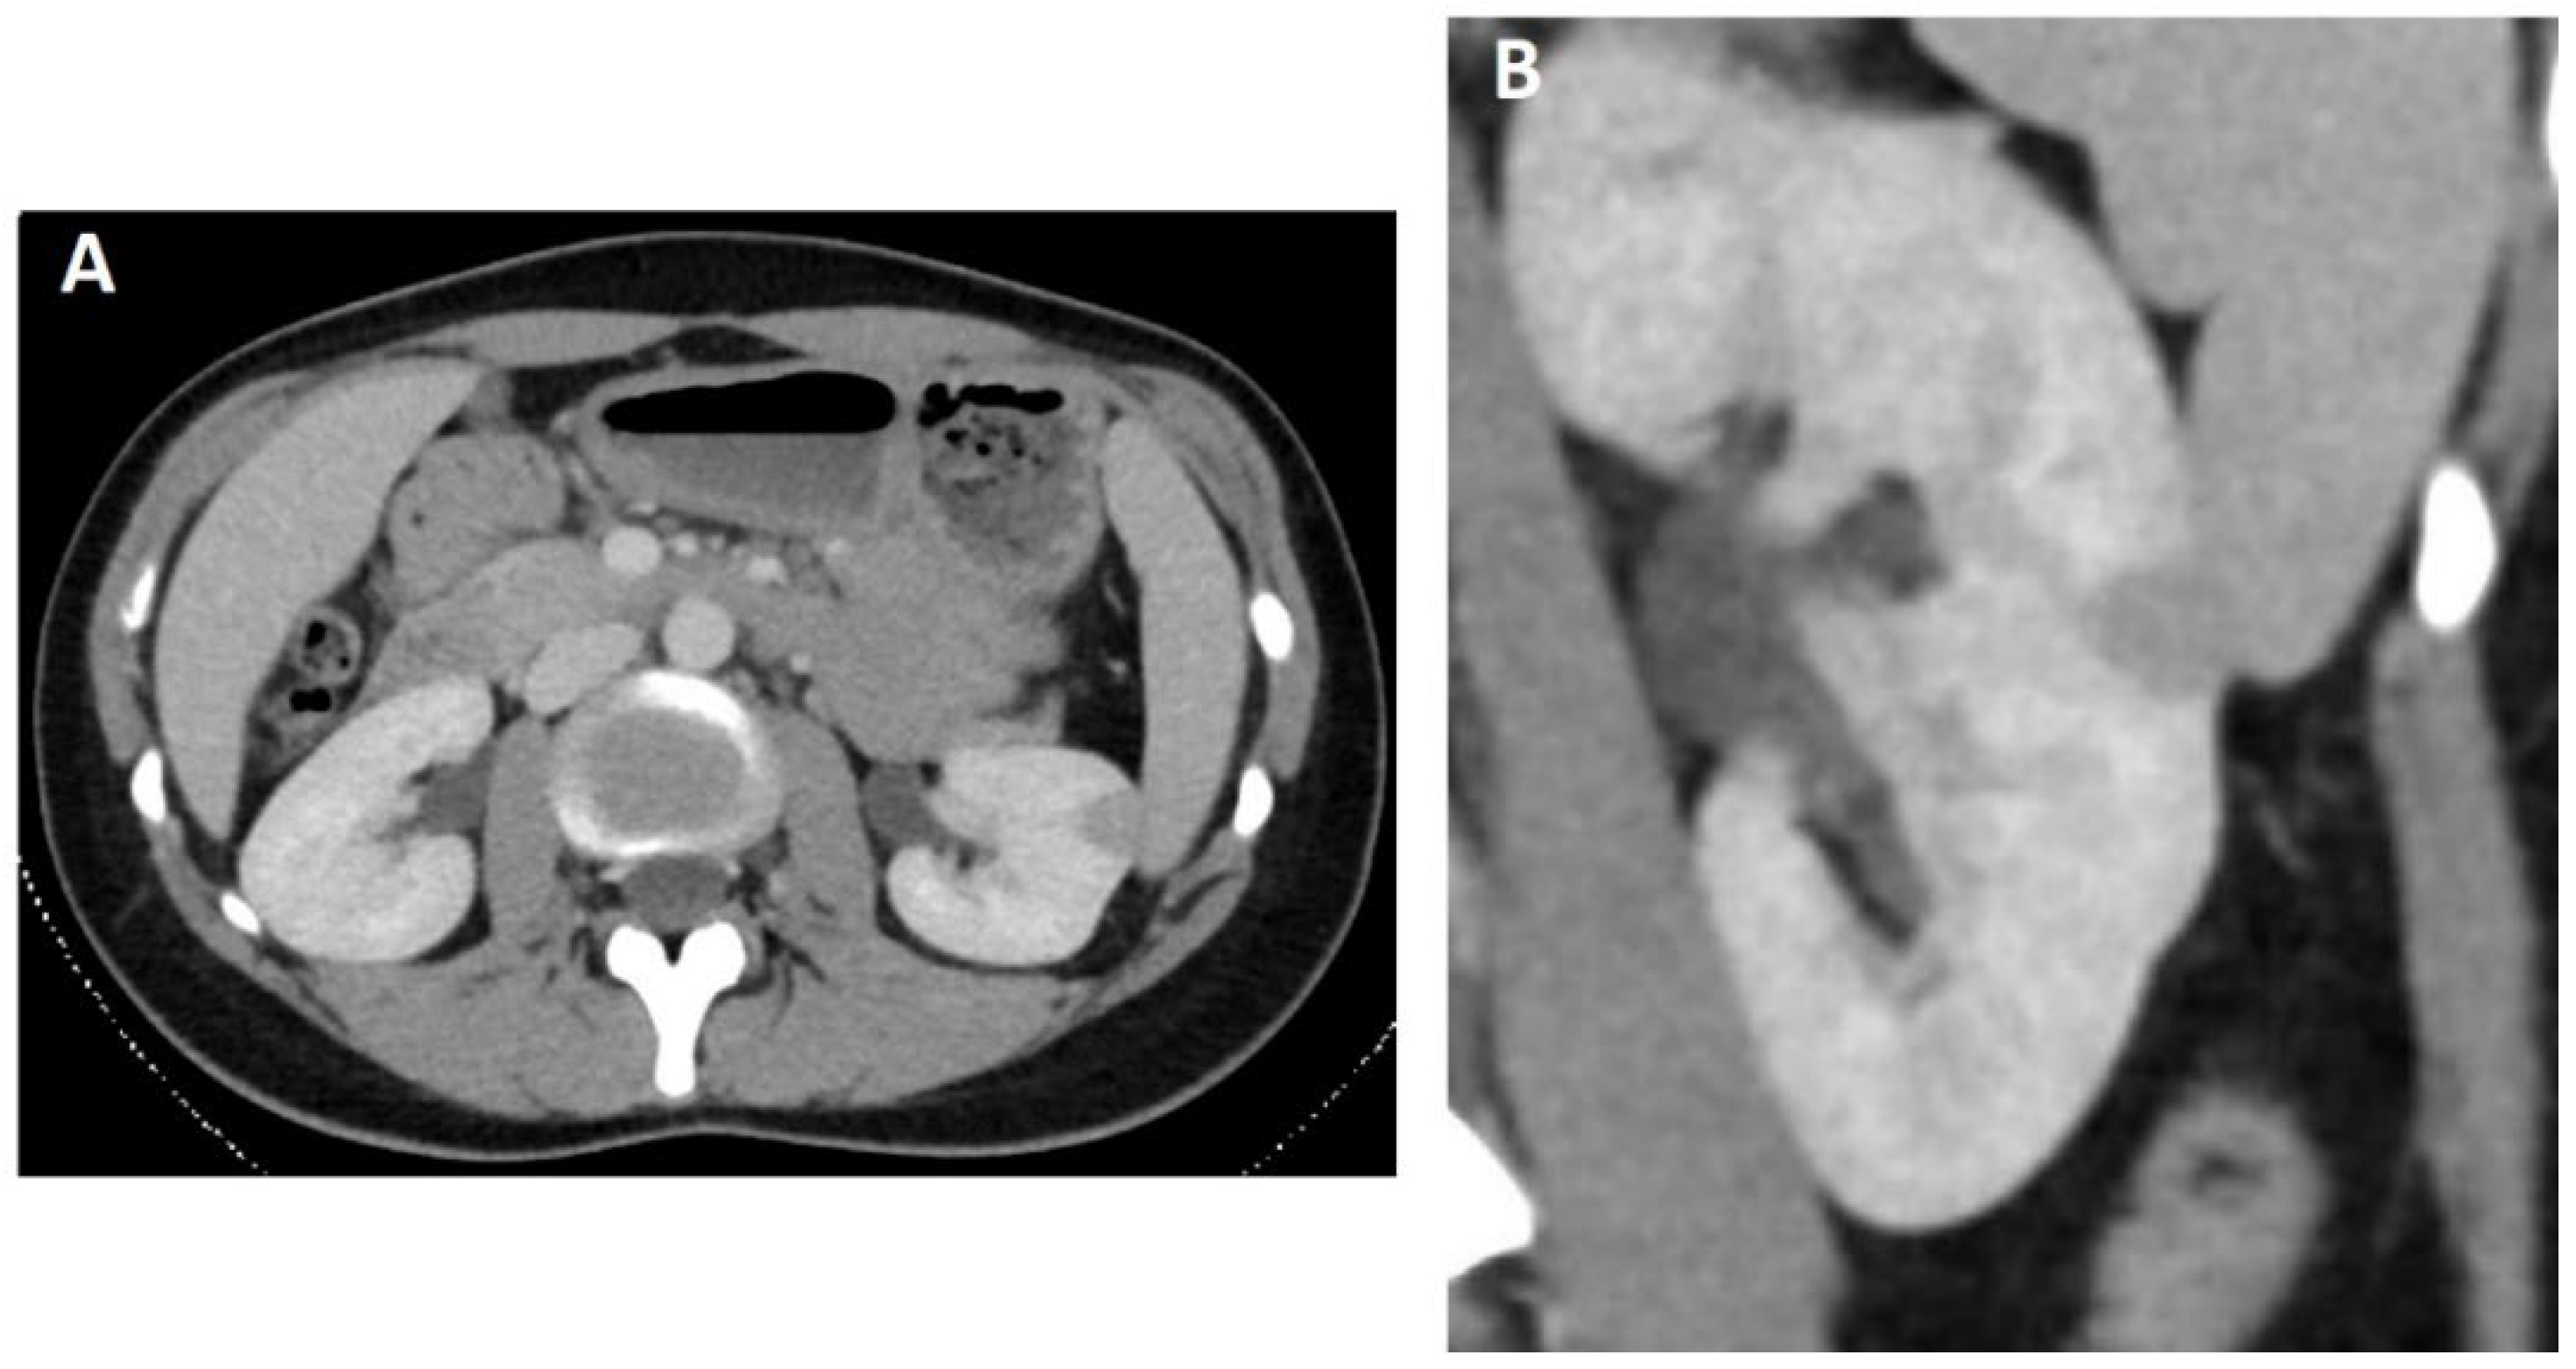

2. Case Study